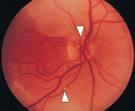

Atendí un paciente que mientras realizaba ejercicio presentó un pérdida súbita de la visión del ojo derecho por al menos 5 minutos,recuperando completamente la misma,esta enfermedad se conoce como Amaurosis Fugax la cual es una obstrcción de las arterias de la retina ,generalmente producidos por coagulos provenientes de la carótida o del corazón,de allí la importancia de tomar inmediatmente los examenes de eco dopler arterial y ecocardiograma para evaluar la carótida y el corazón respectivamente,con lo cual se puede tratar la causa de los émbolos.